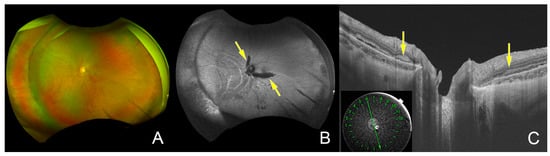

| Current case | 21 | woman | musculocontractural type | dermatan sulfate epimerase | scleral buckling | high myopia, thin sclera | hyperextensible skin and hypermobile joint, prolonged bleeding, bradycardia |